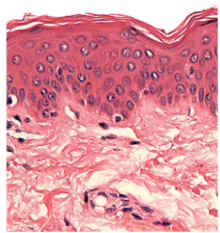

What is this?

Epithelial tissue